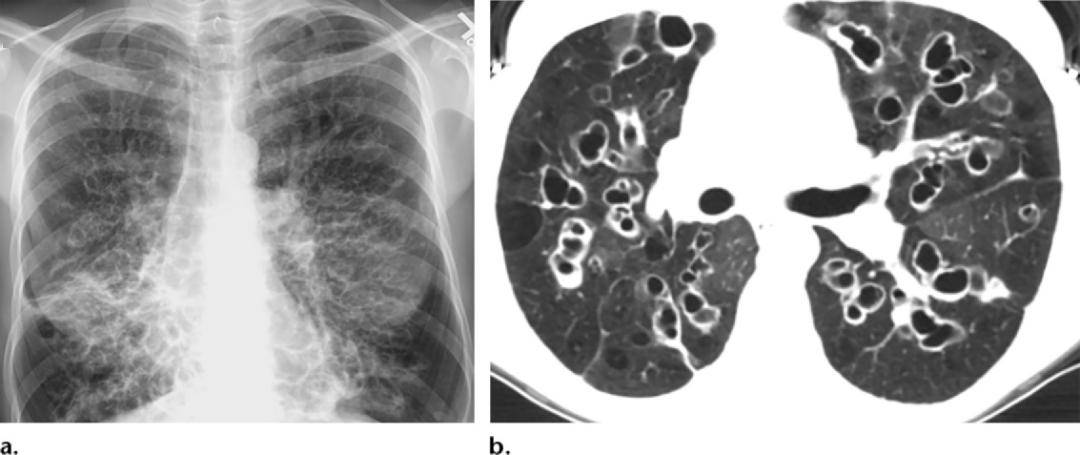

囊状支气管扩张x线片下的气道表现为显著的囊腔,呈卷发状或蜂窝样大小